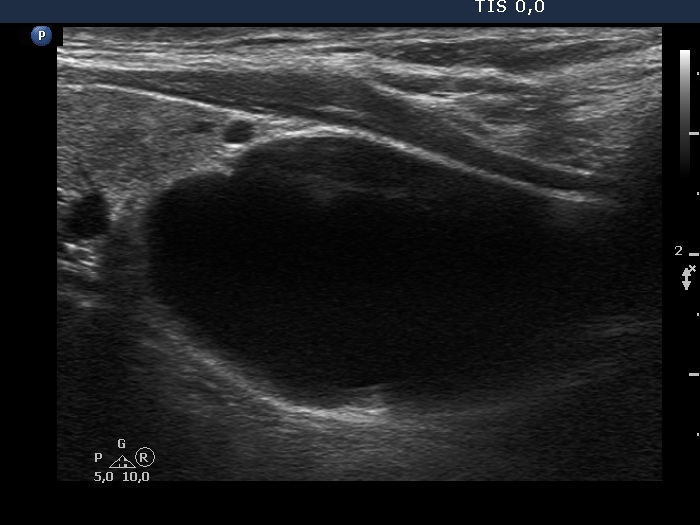

Parathyroid lesions - case 97 (ultrasonographic picture 7)

Right lobe, longitudinal scan

Under the left lobe, longitudinal view. This is an almost completely cystic lesion.